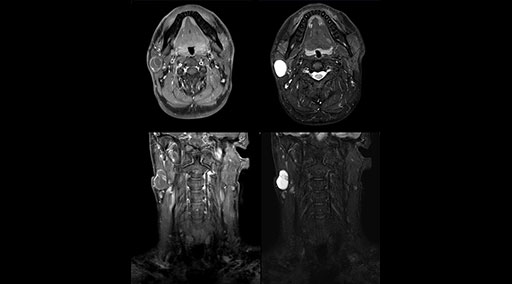

mDIXON TSE fat suppression helps DMG reduce repeats and supports diagnostic confidence

“Our DMG Lisle location includes a cancer center, so soft tissue neck scans, brachial plexus scans, and prostate scans are common. For these exams, mDIXON TSE provides excellent images with and without fat suppression all while helping us reduce repeats and work more efficiently,” Mr. Duffy says.

“With the 2-echo Philips mDIXON TSE the timing is short and the fatsat is very robust. The biggest thing is that you know your fat suppression will be good, even in thin patients or large patients that are off-center,” Mr. Sybesma says.

“mDIXON TSE raises our diagnostic confidence with its homogeneous

fat suppression. Neck exams and rheumatology patients are two examples where mDIXON TSE is especially useful,” Dr. Kaakaji says. “For us it’s also an efficiency boost in exams where we need pre and post T1-weighted images with great fat suppression.”